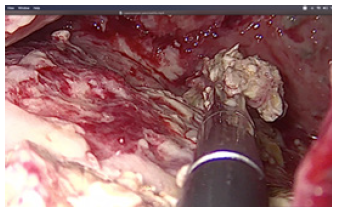

In ten cases we performed laparoscopic cholecystectomy with debridement of pancreatic necrosis. For 18 patients we explored the CBD by choledoscope and extraction of stones was done. The operation was finished with placement of T- tube drainage by laparoscopic approach. In 7 cases was accomplished percutaneous drainage of WOPN under US-control. For eight patients was applied a two-stage procedure. The first step was a placement of percutaneous biliary drainage under US-control and C-arm control. The second step was laparoscopic necrosectomy. A temporary loop ileostomy was performed in 5 cases because of bowel paralysis around the pancreas, paralytic ileus, abdominal distention and worsening of the patients’ condition. Debridement by laparoscopic access was accomplished by transgastric approach or gastrocolic access to enter the lesser sac. Applying a gentle blunt removal of necrotic tissue around pancreas, we take care of blood vessels around the pancreas, and we usually use a bipolar coagulation in case of bleeding from vital pancreatic tissues. We always take a sample from infected tissues for culture and subsequent precise antibiotic treatment (Figure 3).

Debridement of necrotic material was performed by forceps and with a laparoscopic irrigation/suction device with evacuation of infected debris (Figures 4-6).